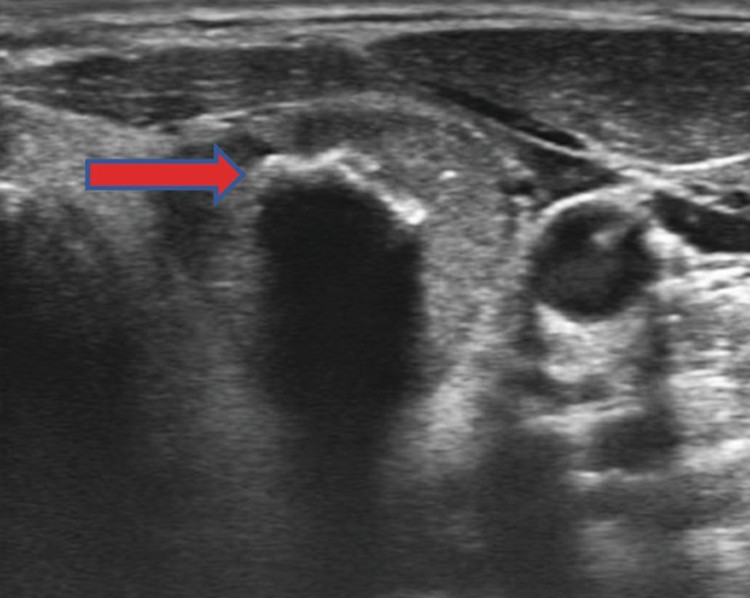

Cần phân biệt kết quả siêu âm phát hiện các vi vôi hóa hay là vôi hóa lớn? Một trong những đặc điểm siêu âm quan trọng nhất gợi ý ung thư là sự hiện diện của các vi vôi hóa, được nhìn thấy dưới dạng các điểm sáng nhỏ có kích thước ≤ 1 mm, xuất hiện trên ảnh siêu âm tuyến giáp.

Do đó, khi có mặt trên siêu âm, vi vôi hóa đại diện cho vùng ung thư tuyến giáp thể nhú. Ngược lại, vôi hóa lớn là những mảng canxi lớn, với kích thước > 1 mm (có thể đến 5-10 mm) có thể xuất hiện bên trong nhân giáp hoặc ở ngoại vi của nhân (gọi là vôi hóa dạng vỏ trứng/ vành), thường được nhìn thấy dưới dạng các điểm sáng lớn trên siêu âm.